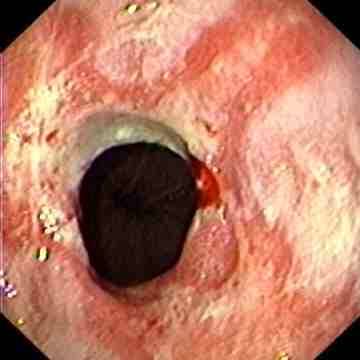

Reflux oesophagitis grade D according to the Los Angeles classification